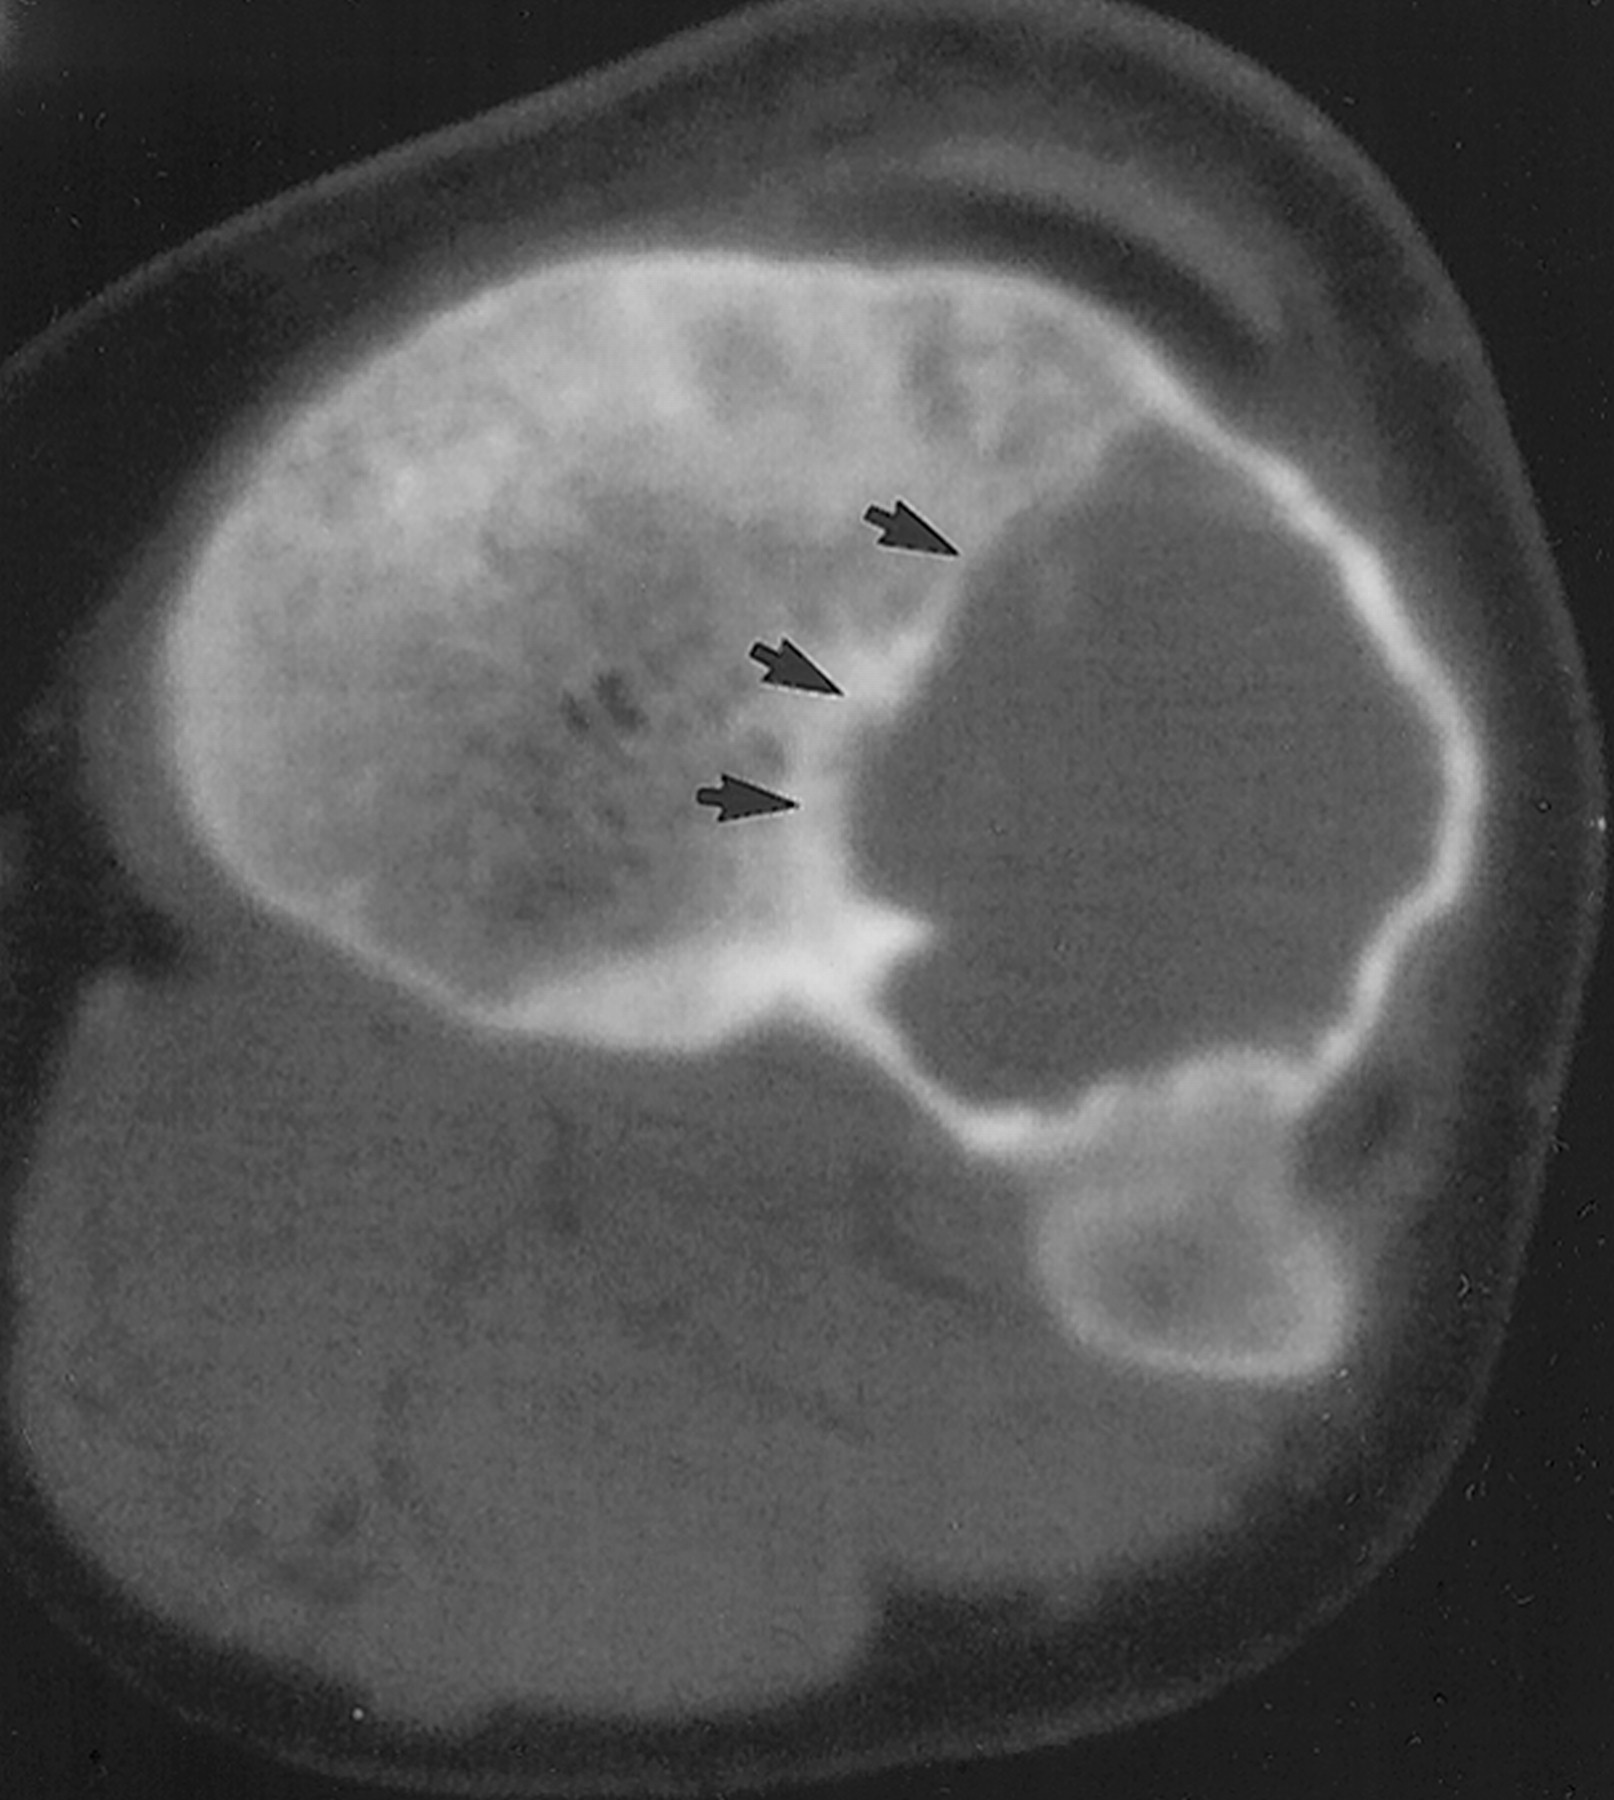

Гигантоклеточная опухоль.

Злокачественная гигантоклеточная  опухоль возникает из доброкачественной (частота 10-20%). После операции возможно появление рецидива опухоли.